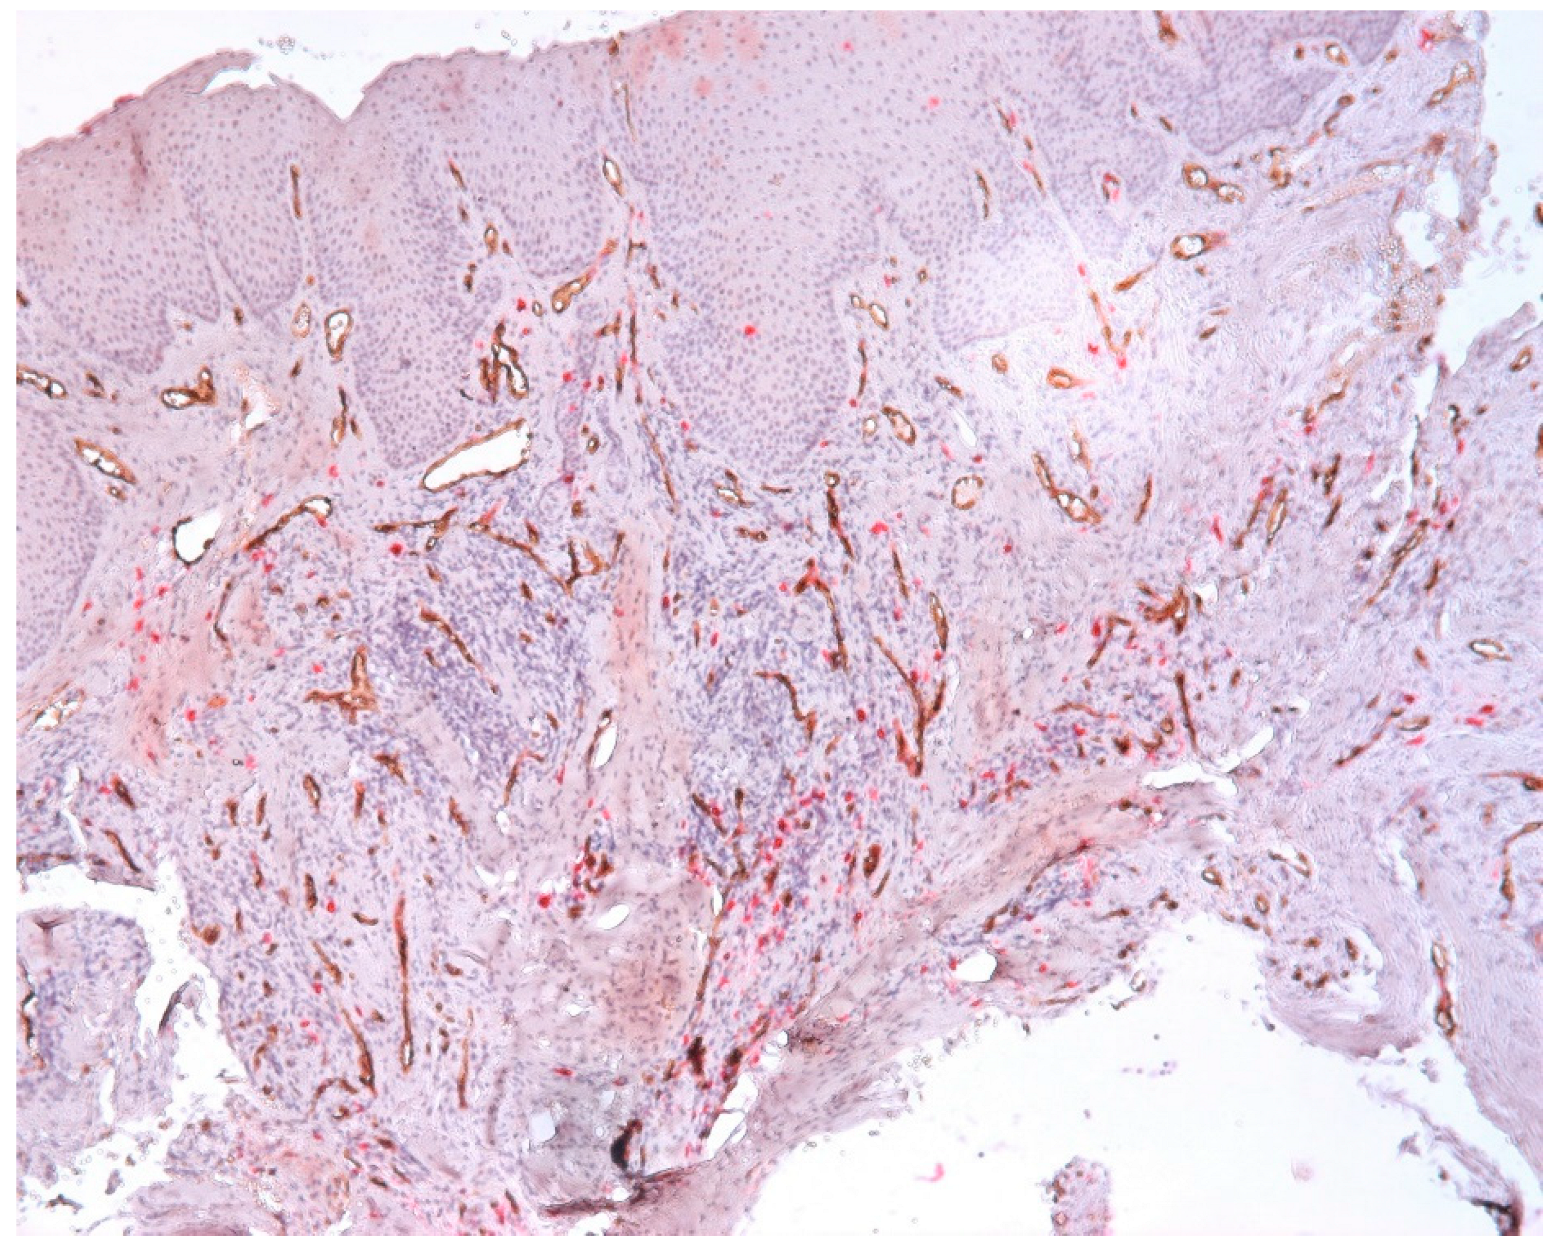

3.3. Aspects of Microvessels

| Intraepithelial Vessels | Subepithelial Vessels | Connective Tissue Vessels |

|---|---|---|

| Mean (SD): 1.4 (2.2) | Mean (SD): 7.8 (6.5) | Mean (SD): 14.9 (3.9) |

| Range: 0.0–9.7 | Range: 0.0–20.3 | Range: 0.0–23.2 |